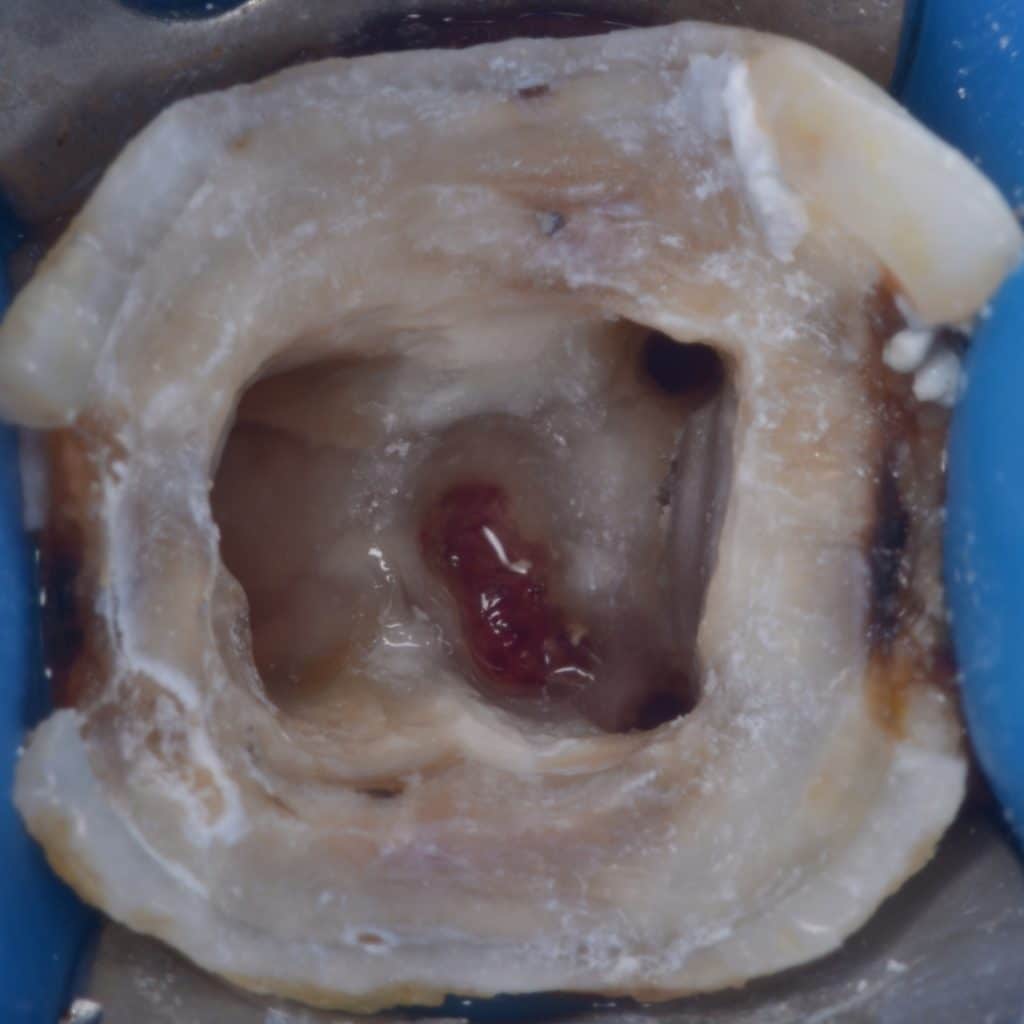

Gutta percha removal

Complete gutta percha removal

Zoom